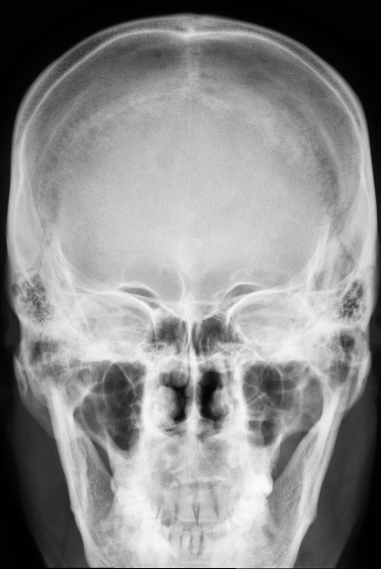

| 2 |

Abnormal fr rt ramus |

Normal |

Incorrect |